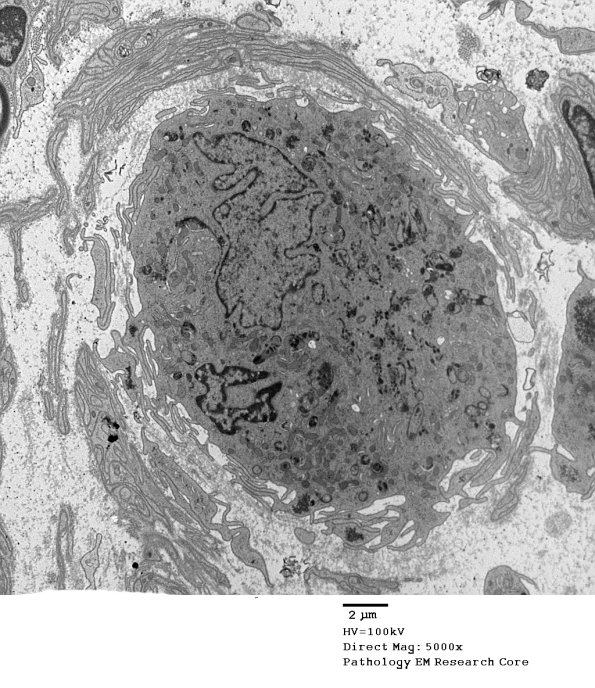

4N2-4 A single very unusual and markedly enlarged cell is noted in the center of the endoneurium of one fascicle. This cell is more than 20 microns in diameter, contains a lobated nucleus and demonstrates impressive autophagy of cellular organelles such as mitochondria and endoplasmic reticulum. The surface of this cell is characterized by numerous filopodia. We have had some difficulties in identifying this cell and determining its importance, if any, to the understanding of this case. It is likely that this cell is a member of histiocytic/macrophage/dendritic cell group.